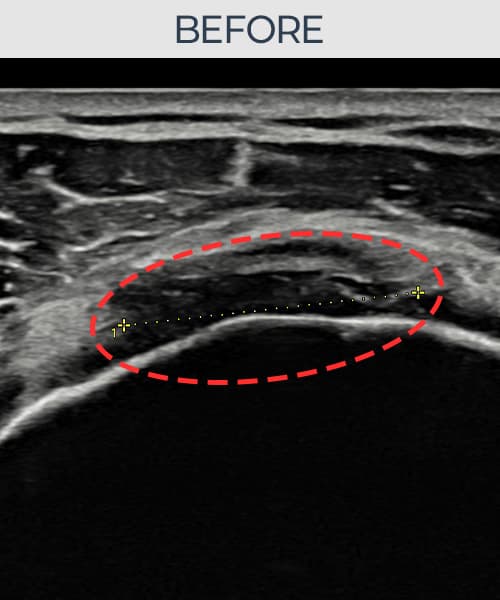

[経過期間: 23.07.18~23.09.14]

[縫縮術] 超音波検査にて左 棘上筋腱 광범위 部分断裂(15mm × 6mm (腱厚の約70%欠損))を確認。縫縮術施行後、腱の連続性が回復し、日常生活に復帰されました。